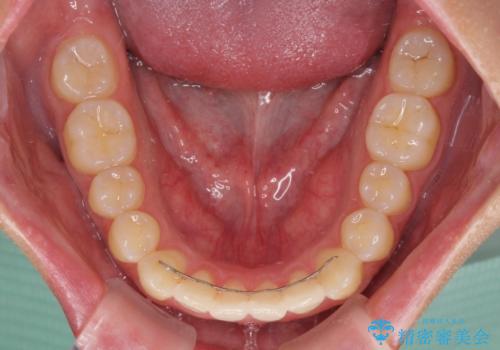

- インビザライン

上下前歯の歯列不正はインビザラインにより歯列を整え、その後に、前歯をオーダーメイドタイプのオールセラミッククラウンにて補綴治療することとしました。

初診時には、歯並びを整えることのみを検討されていましたが、歯列が整うにつれて不自然な色合いが気になるようになり、矯正治療を行ってから補綴治療をする計画を受け入れてくださいました。